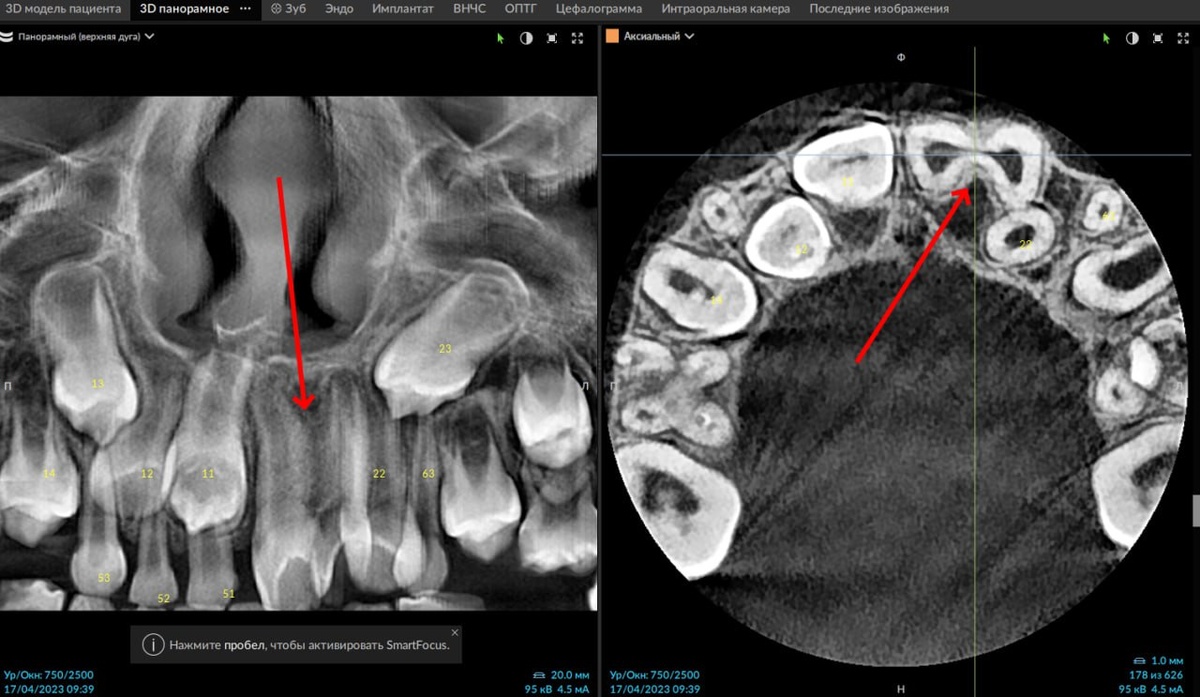

Геминация (удвоение) 2.1 зуба. Клинический кейс

В новом кейсе рубрики «Через призму Х-лучей» разбираем интересное наблюдение от врача-рентгенолога Александра Потапова — случай удвоения зуба 2.1. 🦷

Геминация (удвоение) 2.1 зуба, синоним - шизодонтия (Schizodontia). У данного пациента отмечается неполная геминация (2.1 удвоен, но не образует два отдельных полноценных зуба).

Клиническое значение заключается в повышенном шансе скученности во фронтальном отделе, наличием борозд в коронковой части (зоны, трудно поддающиеся гигиене) и, как следствие, склонности к поражению кариесом. Помимо этого, необычная форма коронки влияет на эстетику в зоне улыбки.